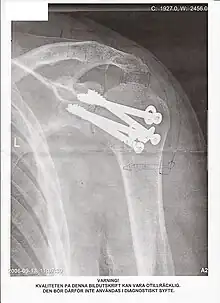

Radiographie d'une épaule ayant subi une arthrodèse

Une arthrodèse est une intervention chirurgicale destinée à bloquer une articulation lésée par l'obtention d'une fusion osseuse (en général de l'extrémité des os) dans le but de corriger une déformation ou d'obtenir l'indolence. C'est souvent une opération non réversible. L'opération inverse, qui consiste à désolidariser des os fusionnés, s'appelle une désarthrodèse.